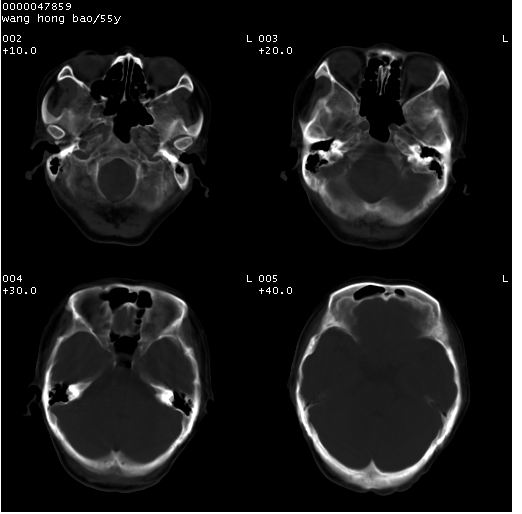

以下是引用dyqct在2008-5-3 23:36:00的发言:[br]桥前池区可疑蛛网膜囊肿。其它未见明显异常。建议做mri。

以下是引用qiushi在2008-5-4 10:10:00的发言:[br]鞍上池前缘突出影为双侧额叶直回;箭头所指为双侧正常之人字缝.[br]桥前池区可疑表皮样囊肿或蛛网膜囊肿,必要时mri

以下是引用zjzjr在2008-5-4 14:50:00的发言:[br]桥前池区可疑蛛网膜囊肿。其它未见明显异常。建议做mri。